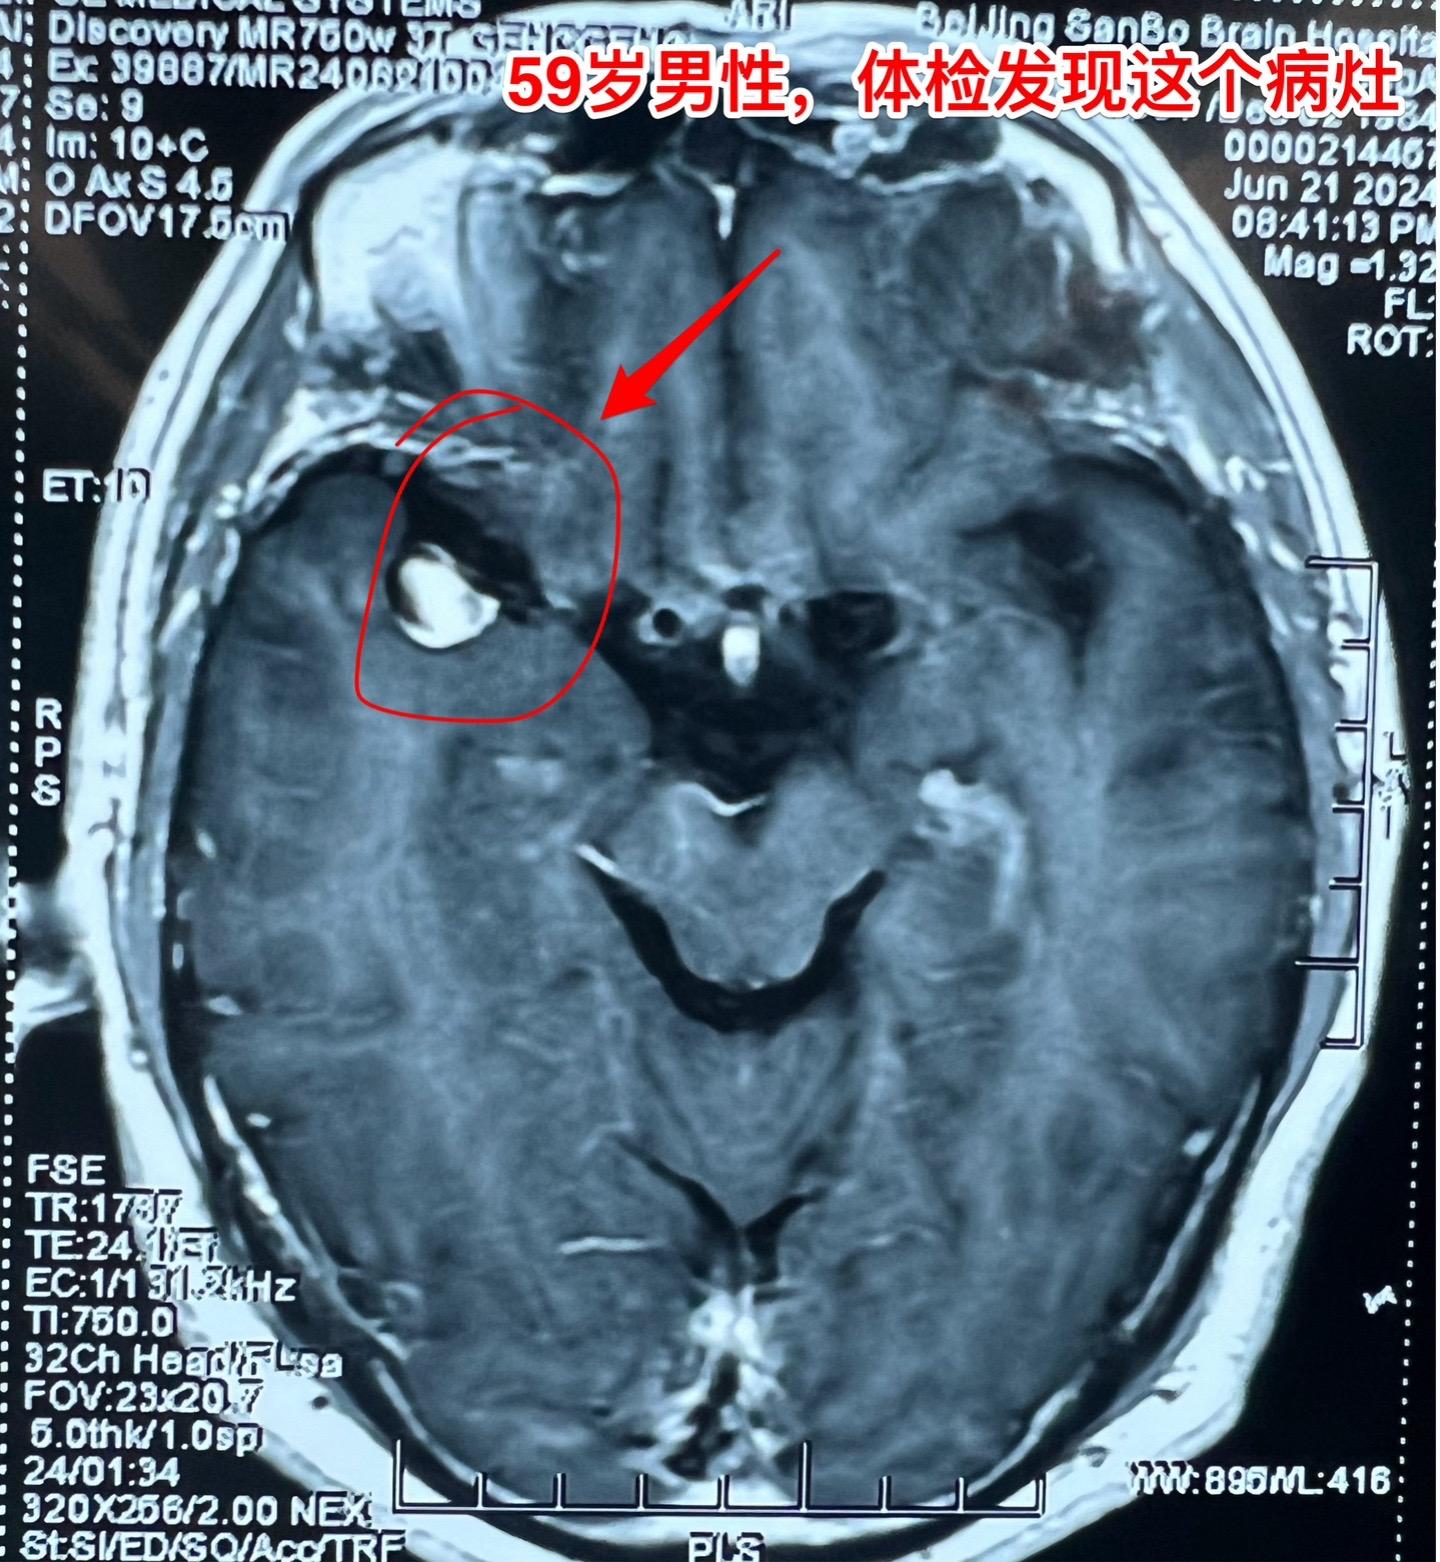

发现未破裂的脑动脉瘤就要作手术吗?慎重!40岁以上的人群中作CTA或者MRA体检筛查脑动脉瘤,发现率是7%!这是未破裂动脉瘤。 未破裂脑动脉瘤的治疗要慎重!要达到国家指南治疗标准才有治疗指征,有治疗指征也不是说必须作手术。 59岁男性,行脑部磁共振检查时发现一个脑动脉瘤,其大小约10x8毫米,位于右侧大脑中动脉,见图。 这个病人从来没有脑部出血病史,这样的动脉瘤需要治疗吗? 这个大脑中动脉动脉瘤直径超过5毫米,根据中国的未破裂脑动脉瘤治疗指南,是